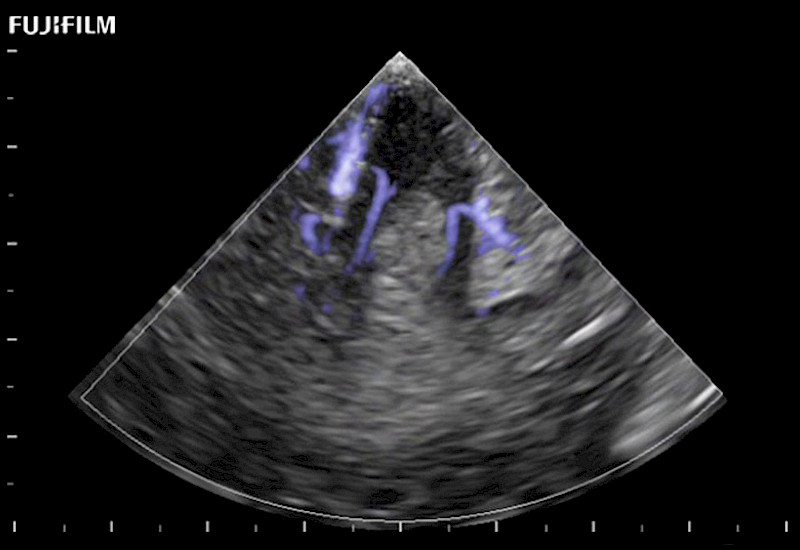

Hockey-stick linear array transducer is the transducer of choice for cervical spine scanning.

Main Specifications: